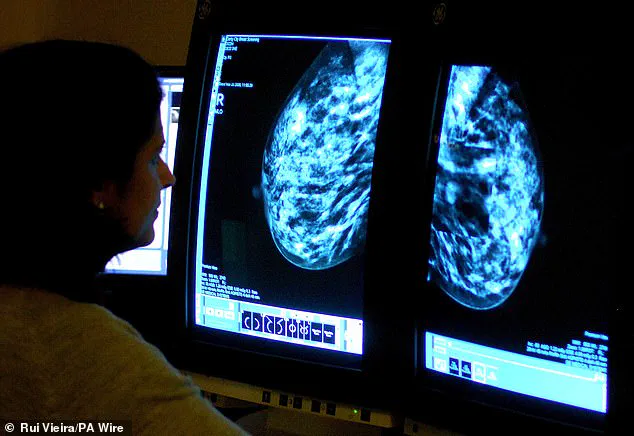

This is a critical point, as research has shown that for many women, especially those with dense breast tissue, screening may be the only way their cancer is detected.

Dense breast tissue, which is common and normal, can obscure tumours on mammograms, making additional imaging—such as ultrasounds or MRIs—necessary.

Dr.

Ramsey urges women to ask their healthcare providers if their breast density is noted on mammograms, a step that could mean the difference between early detection and a late-stage diagnosis.

The debate over breast density is intensifying as evidence mounts that dense breast tissue can obscure cancerous lesions, making them harder to detect on standard mammography.